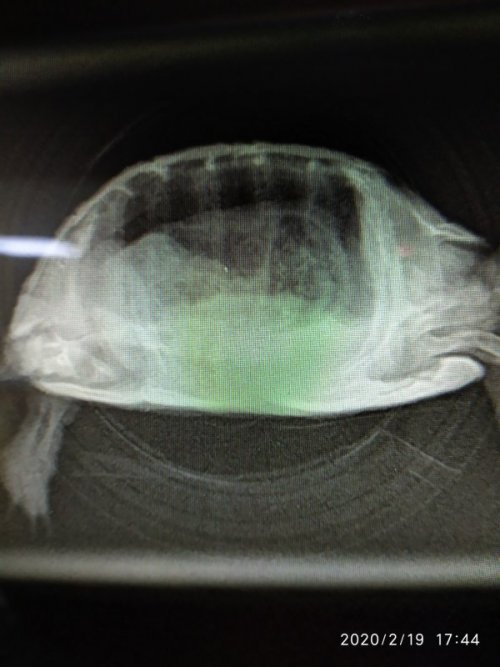

@AlekSandra рентген - дорсо-вентральная проекция + латеральная(боковая) (левая)

Сделали рентген.

Я сейчас выкладываю фото поменьше размером, иначе они не проходят ограничение форума, если какой-то нужен будет покрупнее, скажите я выложу отдельно.

@AlekSandra  в жкт, особенно в желудке, присходит что-то нечто. Переполнен и с большим кол-вом газов, это и давит на легкие (особенно левое)

по этим снимкам пневмонии нет.